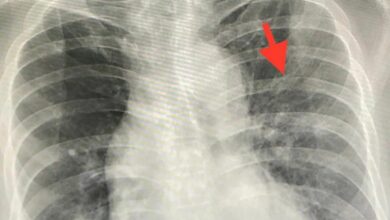

หมอมนูญ เผยพบผู้ป่วยโควิด ติดโควิดซ้ำ ห่างกัน 19 วัน รอบสองอาการป่วยหนักกว่ารอบแรก คาดเป็นคนละสายพันธุ์ รวมถึงผู้ป่วยภูมิต่ำ นพ.มนูญ ลีเชวงวงศ์ ผู้เชี่ยวชาญด้านระบบทางเดินหายใจ โรงพยาบาลวิชัยยุทธ โพส